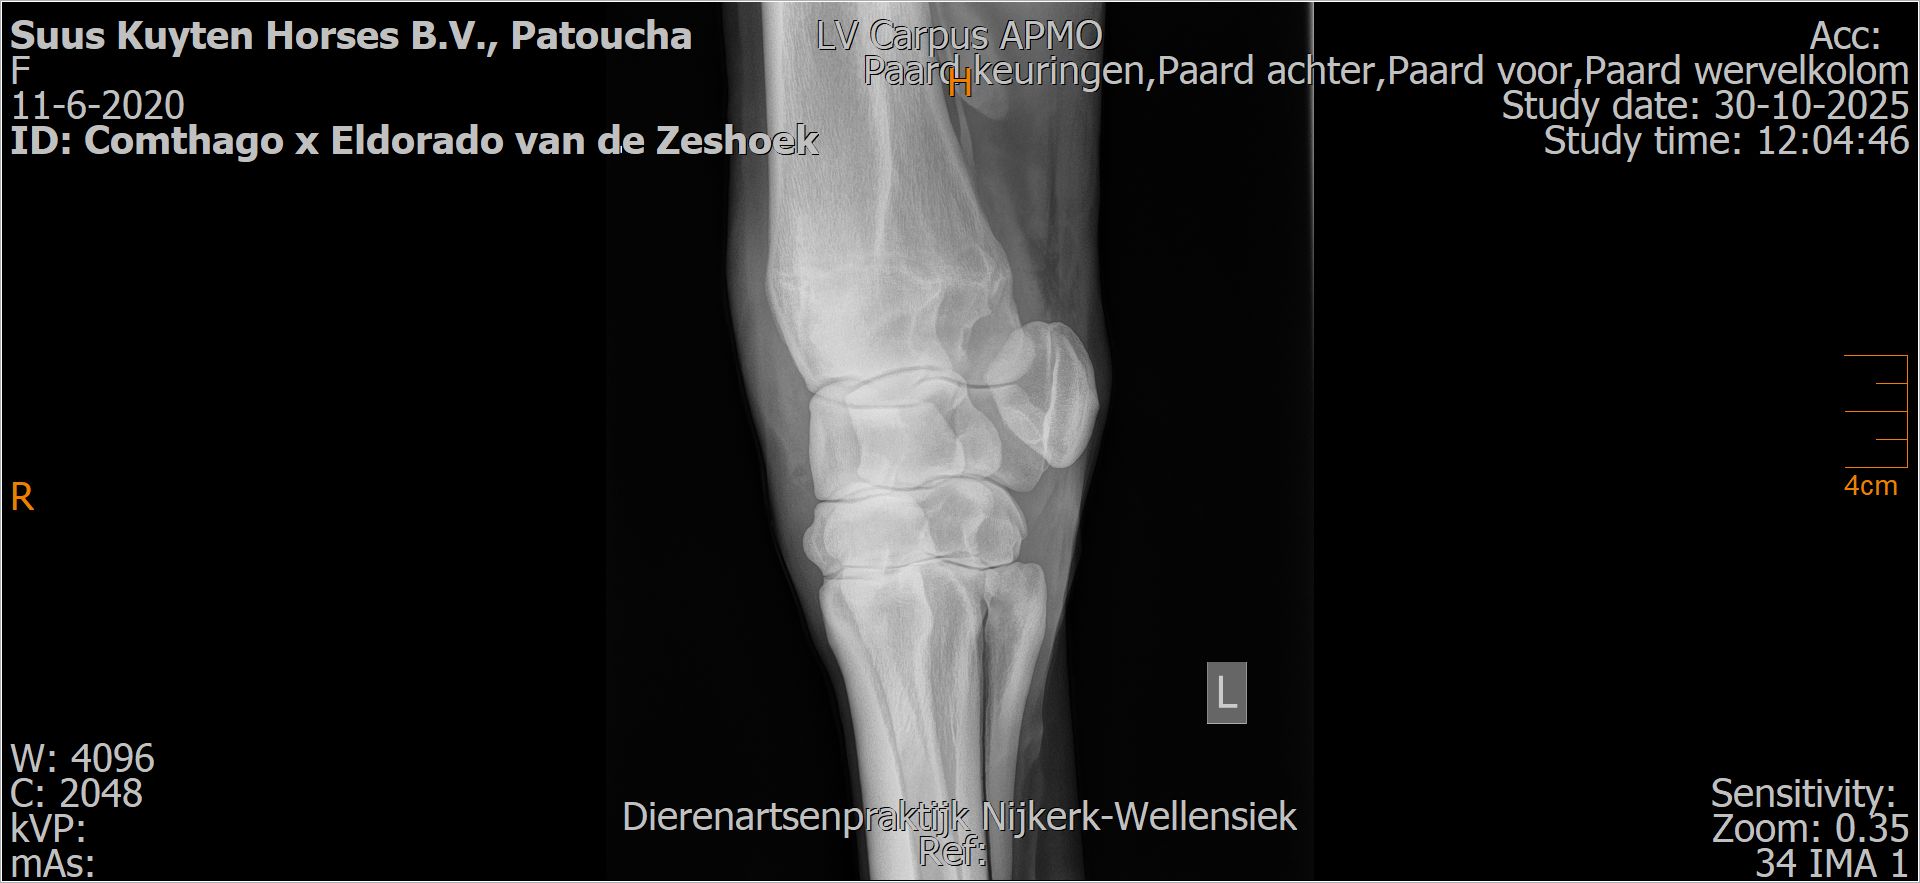

Patoucha

Leeftijd:

7

Röntgenfoto’s